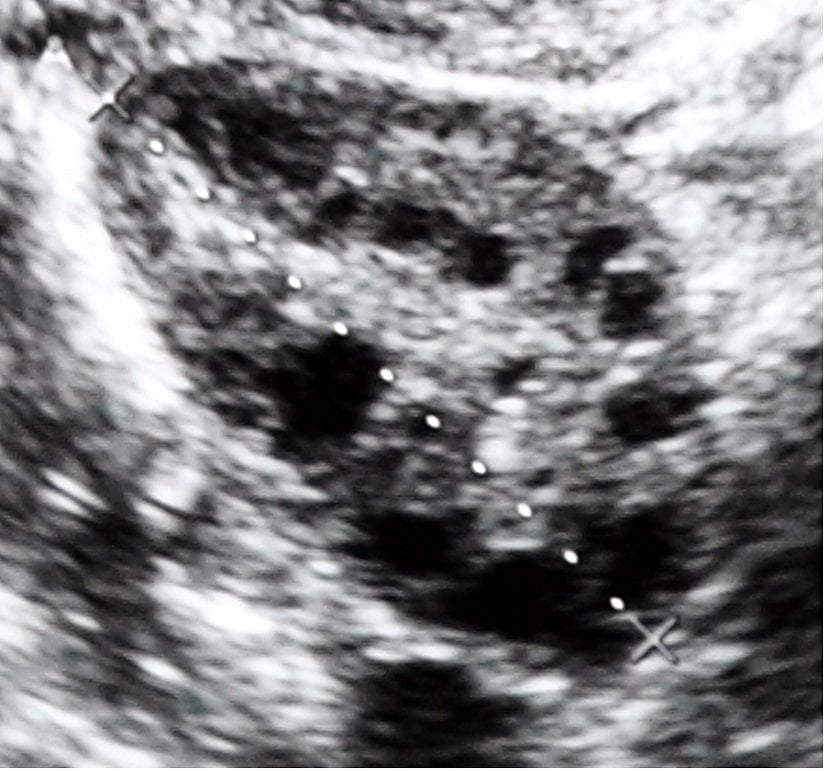

Polikistik Over Sendromu, hiperandrojenizmin (kanda testosteron, dihidrotestonteron, DHEAS gibi hormonların yüksekliği) deri bulguları olan hirsutizm (kıllanma artışı) ve akne artışı, düzensiz menstrüasyon, çok sayıda kistik yumurta, obezite ve insülin direnciyle seyreden bir hastalıklar grubudur. Bu sendromda asıl neden bilinmemekle beraber kalıtımsal ve kalıtımsal olmayan intrauterin (rahim içindeki dönem) ve extrauterin (doğum sonrası dönem) faktörler suçlanmaktadır. Androjen hormonların artışı yumurta oluşumunda düzensizliklere yol açıp özellikle yumurtanın kalitesini olumsuz şekilde etkilemektedir. Sonuçta çok sayıda erken evrede ve işlevsiz, kistik yapıları andıran yumurtalar oluşmaktadır. Evre ve kist yapıları, ilerleyen kısımlarda açıklanacaktır.

Polikistik Over Sendromu yumurtanın döllenmeye kadar içinde korunduğu ve beslendiği folikül yapılarının diğer bir deyişle kistlerin çok sayıda, küçük boyutlarda, yapının çevresine inci tanesi gibi dizilmesiyle ve içindeki yumurtanın kalitesinin de çok düşük olmasıyla karakterize bir hastalıktır. Bu sefer de yumurtlama sürecini bilmek konuyu daha kolay anlamak açısından yardımcı olacaktır.

Yumurtalık organı her yumurtlama döneminde içerisindeki yumurta hücrelerini, besin ve korunma olanakları yüksek olan kistler içinde üretmektedir. Yumurta hücreleri özellikle LH (lüteinleştirici hormon) ve kısmen de olsa FSH (folikül stimülan hormon) miktarındaki artış sayesinde beslenip büyümeye başlamaktadır. Her hormon-hücre arası ilişkide olduğu gibi burada da reseptör düzeyinde etkileşim görülmektedir. Kısaca LH ve FSH, yumurta hücresindeki reseptörünlerine bağlandıkça o hücrenin daha iyi beslenmesini ve büyüyüp gelişmesini sağlayacaktır. Yumurtalıktaki bu yumurta hücreleri belli bir büyüklüğe geldikten sonra (sekonder folikül) birbirleriyle besin erişimi açısından rekabet etmeye başlarlar. Bu rekabet hücre yüzeyindeki LH'nin ve FSH'nin reseptör sayılarına bağlıdır. Bu hormonlardaki azalma eğilimiyle sonuçlanan dalgalanmalar periyodu, LH ve FSH reseptörüne en çok sahip olan yumurta hücresini avantajlı hale getirecektir çünkü reseptörden zenginliği en fazla olan bu yumurta beslenebilecekken diğer reseptör sayısı az olan yumurta hücreleri gittikçe zayıflayacak ve zamanla kullanışsız bir hale gelecektir. Sonuçta yumurtlama öncesi dönemde bir tane çok iyi gelişmiş kist (Graaf folikülü)-aslında çok iyi gelişmiş yumurta hücresi olarak da düşünülebilir- ve birçok ufalmış kist ortaya çıkacaktır.

Polikistik Over Sendromu'nda androjen hormonların fazlalığı, LH ve FSH gibi hormon dalgalanmalarının karakteristik seyrinin dışına çıkmasına neden olup rekabet ortamını reseptör etkileşiminden bağımsız bir hale getirmektedir. Sonuçta yumurta hücreleri benzer boyutlarda ve gelişememiş bir durumda kalmaktadır.